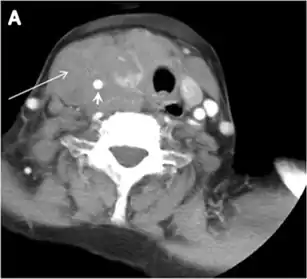

Fig. 9. A 58-year-old male patient with persistence PTC at thyroid bed with hypervascular nodal metastasis. a–c Transverse greyscale and colour Doppler neck ultrasound demonstrate hypoehoic soft tissue in the left thyroid bed (white arrow in a). There are a heterogeneous enlarged lymph nodes at level 2 and 3 with markedly increased vascularity (white arrow in b and c). d–f Enhanced axial CT images of the neck demonstrate a 2.7 × 1.4 cm hypodense soft tissue lesion anterior to the left carotid sheath (white arrow). There are left-sided enhancing abnormal and enlarged lymph nodes at cervical level 2 and 3 (black arrows).[1]